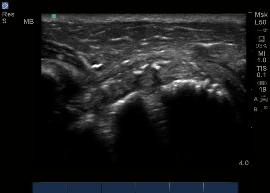

Longitudinal axis, Greater Tuberosity should always

be demonstrated in profile.  Note the layers of the

Supraspinatus Tendon as striated echos, and the

ABOVE: Image of the Supraspinatus tendon in its

Subacromial/Subdeltoid Bursa as a homogeneous

echogenic layer resting over the Supraspinatus

Tendon and courses laterally over the Greater

Tuberosity.